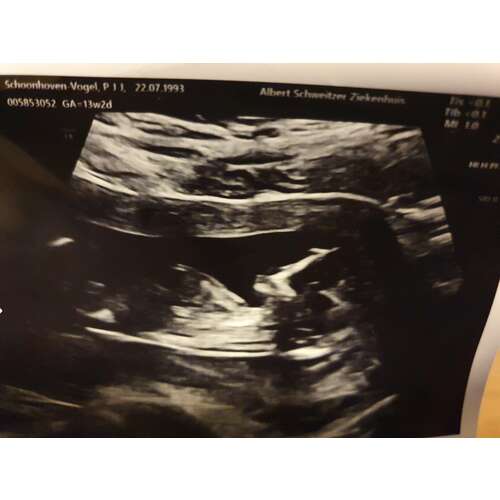

13 weken echo, foto van 13+2. Iemand een idee? 💗💙 16e de geslachtsbepalingsecho

Op advies zet ik m hier ook nog even in🤭🤗 wie kan het al zien? Echo is van de 13 weken echo vandaag 13+2. Denk zelf meisje te zien